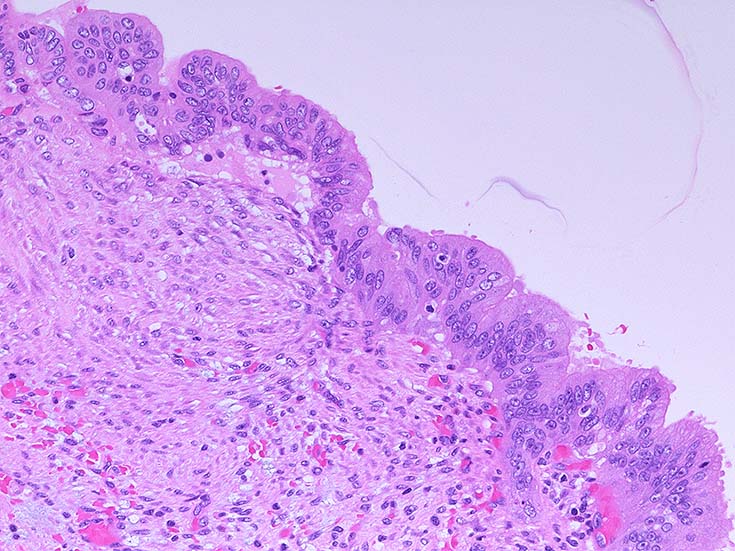

膵上皮内腫瘍性病変 pancreatic intraductal neoplasm(PanIN)*16

Low-grade PanINとhigh-grade PanINの分類

high-grade PanIN

PanINの図譜はJohns Hopkins The Sol Goldman Pancreatic Cancer Research CenterのHome page*19から引用.

2. PanIN-2, PanIN-3;

• TP53の不活化--PanINでのIHCでは機能喪失が,PanIN3のみで観察される. 膵癌発がん過程の遅い段階に出現する事象.